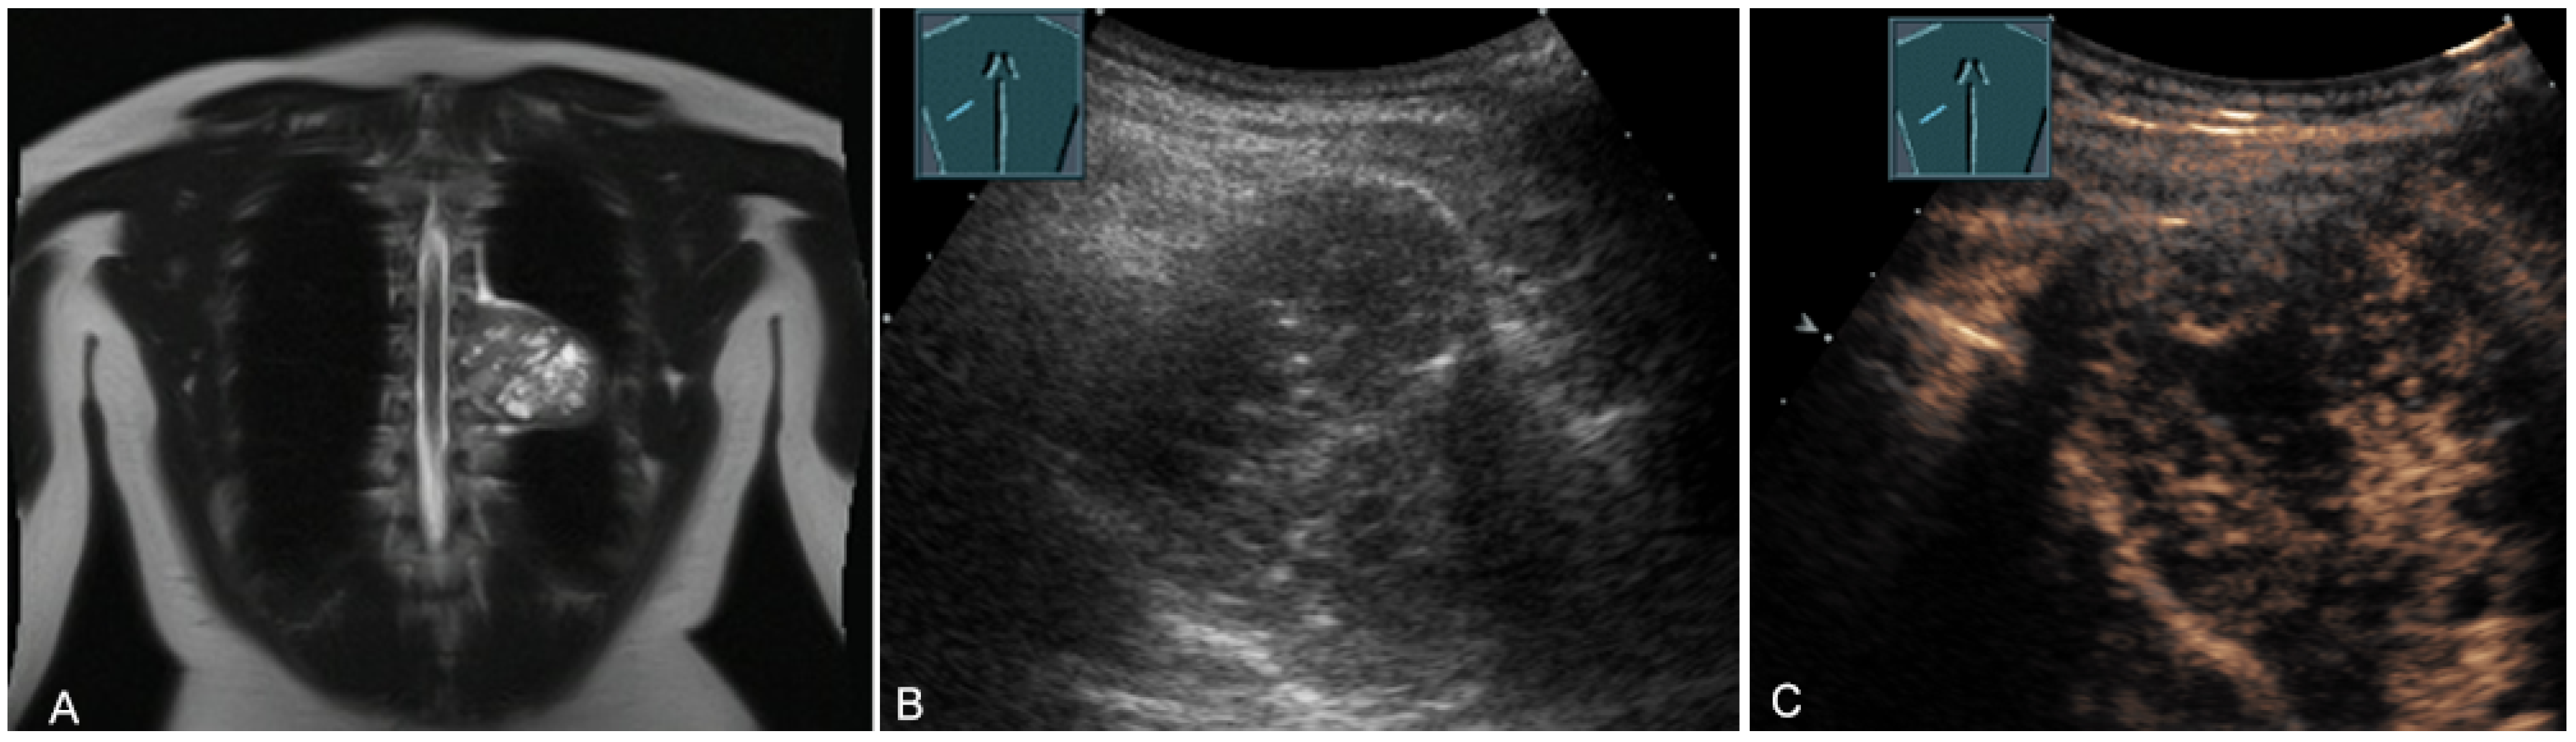

Figure 21.

A young patient with tumor formation in the anterior mediastinum on CT (provided by Prof. Dr. Andreas H. Mahnken, Marburg, Germany) (A), B-mode US (B), and CEUS (C), confirmed by biopsy as Hodgkin’s disease.

Figure 22.